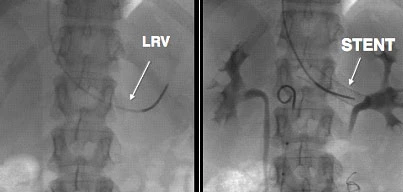

Molte donne convivono con questi sintomi per anni senza ricevere una diagnosi corretta, perché il varicocele femminile può essere difficile da individuare con i normali esami ginecologici. Tuttavia, riconoscerlo è importante perché oggi esistono trattamenti mini-invasivi che possono risolvere il problema in modo efficace e sicuro, restituendo benessere e sollievo duraturo.